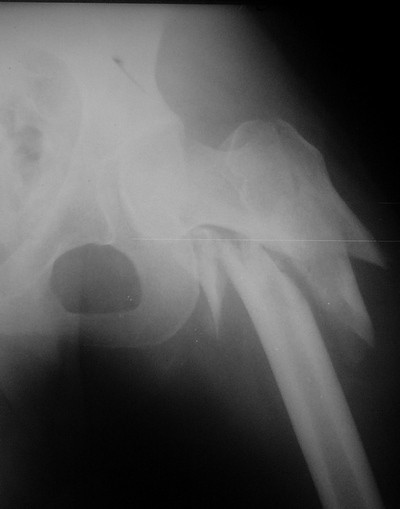

Мы закончили репозицию отломков бедренной кости в аппарате (рис. 1, 2) у нашей пациентки (http://weborto.net/forum/1200869039/index_html) и на прошлой неделе сделали ей вторую операцию. Штифт удалось ввести закрыто. Верхний шеечный винт держался очень плохо, поэтому мы его убрали и решили не ставить. Нижний держал очень плотно. Рентгенограммы после операции прилагаю (рис. 3,4). Пока не получилось сделать нормальный аксиальный снимок (больная с трудом сгибает и отводит ногу в тазобедренном суставе). Пока сделали боковую проекцию в положении на здоровом боку со сгибанием здоровой ноги.

Имя     : рис. 2.jpg

Тип     : image/jpeg

Размер  : 22149 байтов

Описание: отсутствует

Url     : http://weborto.net:8080/pipermail/ortho/attachments/20080216/c8b24fe3/attachment-0005.jpg